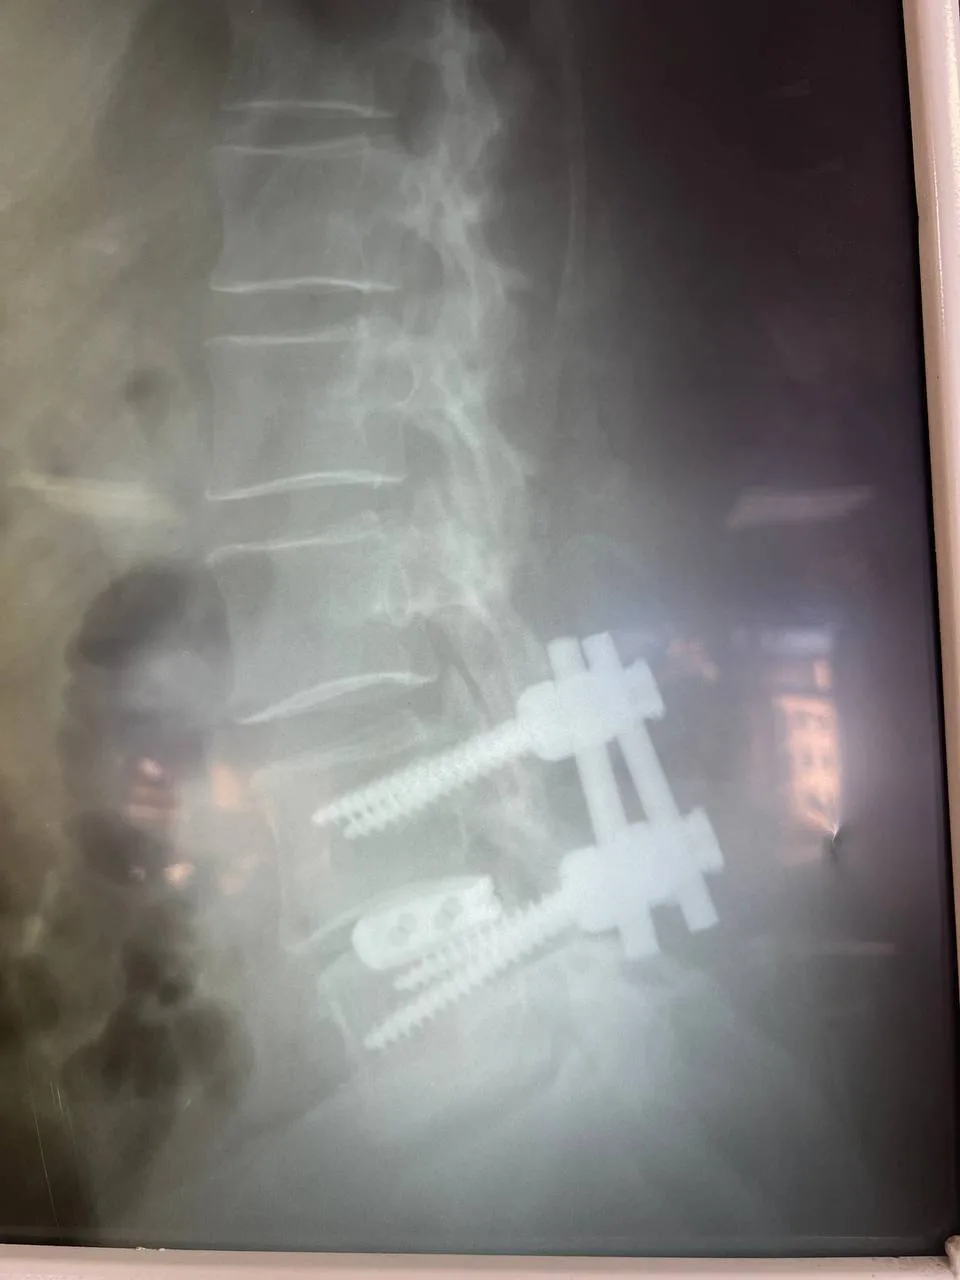

Во время хирургического вмешательства врачи устранили сдавливание с двух сторон, удалили грыжу и заменили поврежденные диски имплантами. Используя микрохирургическую технику, оптический прибор и специальный инструментарий, специалисты ликвидировали компрессию дурального мешка и сегментарных нервов. Кроме того, медики исправили смещение позвонка. Для стабилизации позвоночника установили конструкцию из четырех титановых винтов и двух балок.

Операцию выполнила бригада под руководством нейрохирурга Евгения Дронова.